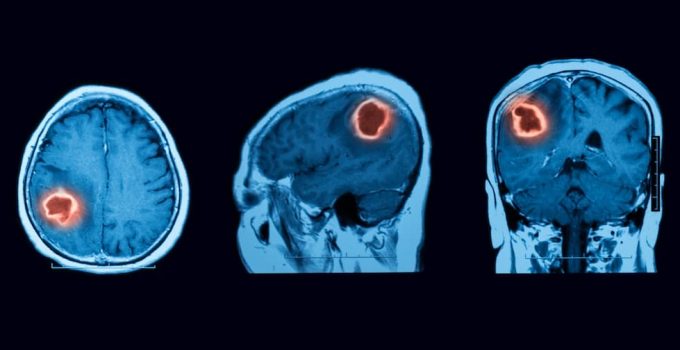

39+ Benign Brain Tumor Ct Scan PNG. They are rarely known to assume metastatic or cancerous form as are malignant brain tumors. Brain ct scans may be done with or without contrast. contrast refers to a substance taken by mouth or injected into an intravenous (iv) line that a ct of the brain may be performed to assess the brain for tumors and other lesions, injuries, intracranial bleeding, structural anomalies (e.g., hydrocephalus.

Depending on the origin of cancer cells and how they behave, who classifies from benign tumor (least aggressive) to malignant (most aggressive).

Brain tumors are either malignant (harmful) or benign (nonharmful). A brain tumor is an abnormal growth of tissue in the brain or central spine that can disrupt proper brain function. Depending on the origin of cancer cells and how they behave, who classifies from benign tumor (least aggressive) to malignant (most aggressive). A brain tumor occurs when abnormal cells form within the brain.